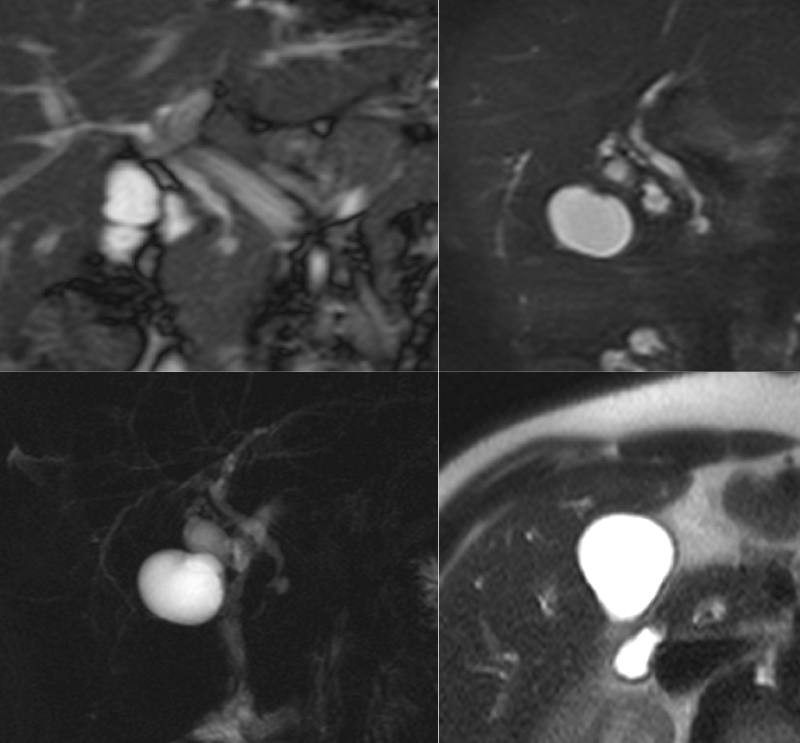

Редкая штука - дивертикул общего желчного протока. Формально - это киста 2 типа по Тодани, но не все исследователи согласны, что это - аномалия, а не приобретенное состояние.